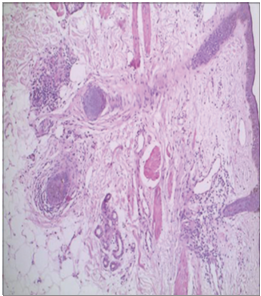

Orofacial Granulomatosis Masquerading as Borderline Tuberculoid Leprosy – A Rare

Case Report

[Sanchita Singhal, Nitin Chaudhari, Swapna Sheth]

Orofacial granulomatous disease is characterized by non-necrotizing granulomatous inflammation of the oral and

maxillofacial region. Clinical findings include labial inflammation, perioral and mucosal inflammation, mouth ulcers,

and gingivitis. Leprosy is a chronic, granulomatous, and multisystem disease and the involvement of lips is an extremely

rare entity that can be mistaken for a variety of other granulomatous conditions. Hence, histopathological examination is

necessary in such a case scenario to overcome the challenges that a professional has to face. Herein, we report a patient who

presented with chronic asymptomatic swelling of the left cheek and upper lip which was later histopathologically confirmed

to be a case of orofacial granulomatosis.

Keywords: Orofacial granulomatosis, Crohn’s disease and sarcoidosis